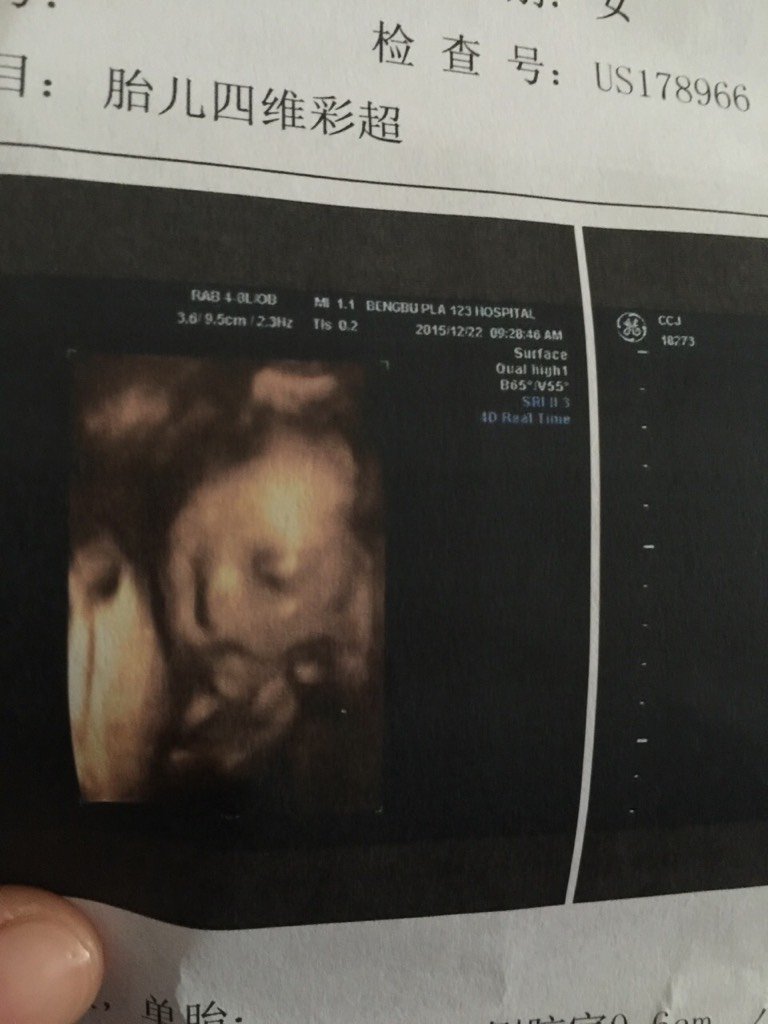

楼主

萌神小Baby

宝宝9岁9个月6天 LV.7因为我的羊水偏少,肚子里还有胀气有泡泡,所以照的模糊。完整健康就满足啦~

雪儿妈咪斌仔爸比:好模糊呀 我家照的很清晰

宝宝9岁9个月6天 LV.73.7cm

゛阳光下、为谁回眸_btFE:宝妈羊水现在多少